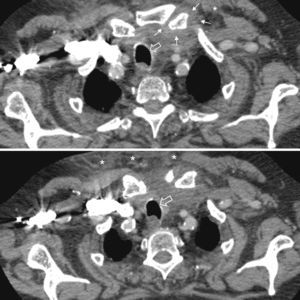

Case 5. Male 55 years. He consulted for a painful swelling of the left chest, of 24h of evolution. Four days before he consulted for atraumatic left shoulder pain. He presented erythematous and painful swelling of the sternoclavicular joint, fluctuating and with sharp edges. Ultrasonography showed capsular distension and PDS (+) both intracapsular as extracapsularly. A superficial abscess of the joint was also identified. A CT scan confirmed the findings and also detected involvement of the distal clavicular sternocleidomastoid body (Fig. 2 Surgical drainage was required. S. aureus was isolated in the culture.